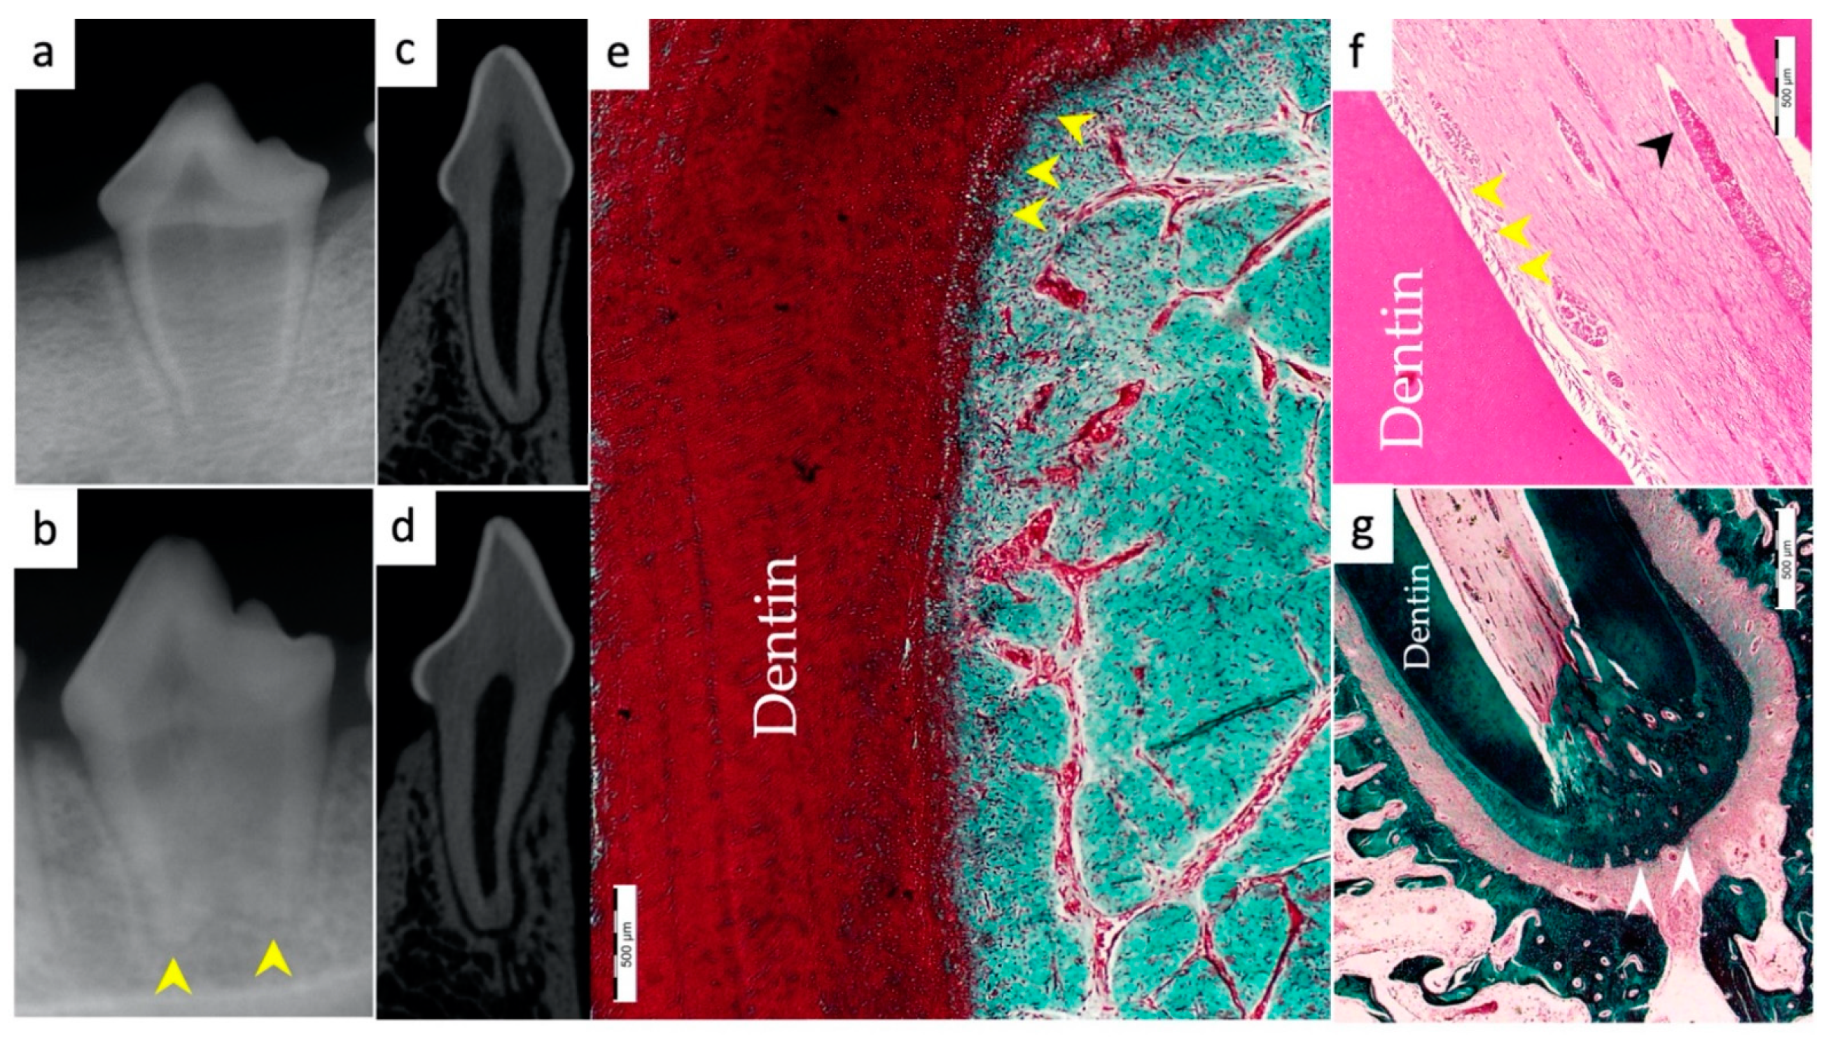

3.1. Hard Tissue Deposition

3.2. Type of Hard Tissue Formed

3.3. Vascularization and Formation of Vascularized Soft Connective Tissue

3.5. Apical Closure

3.6. Positive and Negative Control Groups